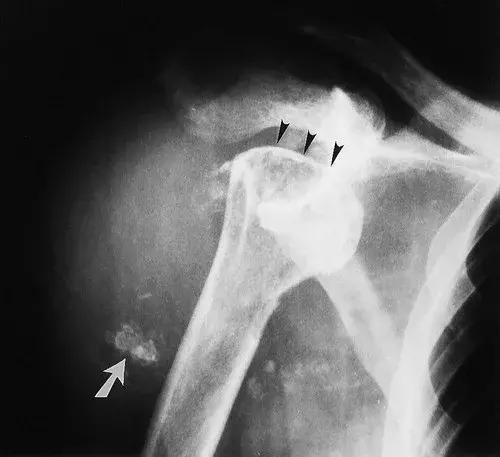

图2: 76岁女性,初步诊断软骨肉瘤,最终为神经性肩关节。 (a)X线片显示了神经病理性关节病的经典发现,包括类似截肢(箭头),脱位和碎片(箭头)的肱骨头破坏。 (b)T2加权自旋回波MR图像(2,550/96)显示大的关节积液和骨化碎片(箭头),位于充满液体的关节中,而不是在软组织肿瘤中出现。 (c)CT扫描显示扩张的关节囊内的碎片(箭头)。